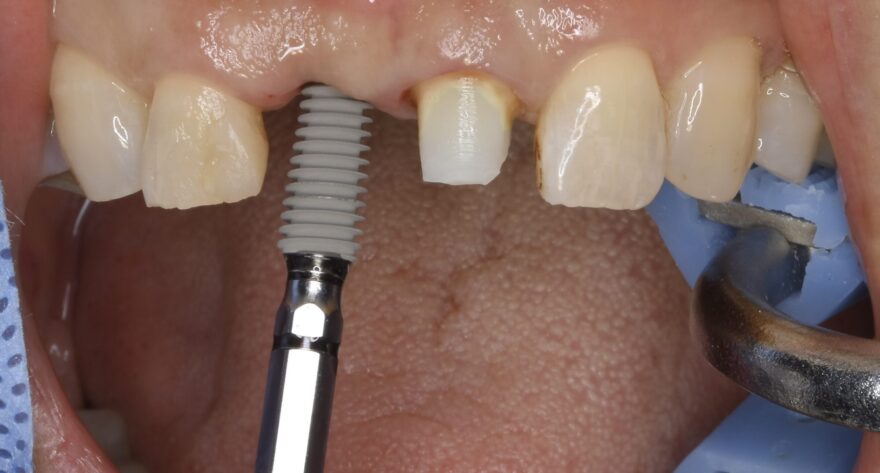

オペ日の口腔内写真とCT

失った前歯の箇所の歯茎の骨が痩せていることが分かります。

直径4ミリほどの穴を開けていきます。

ここまでのオペ時間はわずか10分。

出血もありません。

シミュレーションと同じ位置にインプラントが埋め込まれていることが分かります。